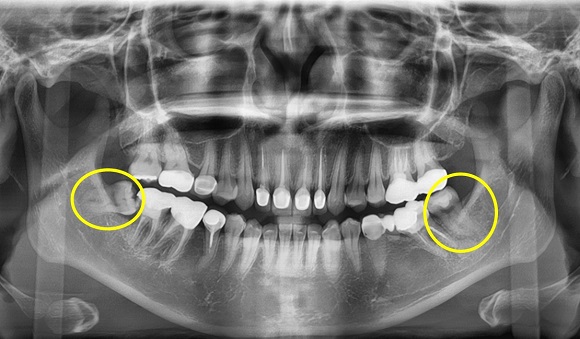

사랑니란 치아의 가장 안쪽에 위치한 큰 어금니 중 하나다. 가장 뒤늦게 자라는 치아로 양쪽으로 위, 아래 하나씩 총 4개가 있지만 나타나는 정도는 개인차가 있다. 일반적으로 드러난 사랑니와 숨어 있는 사랑니로 나뉘는데 보통 성인의 경우 28개 치아 개수에 비해 턱이 작기 때문에 사랑니가 온전히 나오지 못하고 누워서 나거나 삐뚤게 되는 경우가 많다. 잇몸 안에 묻혀 보이지 않는 사랑니의 경우 주변 치아 옆 뿌리를 손상시키거나, 잇몸을 붓거나 아프게 할 수 있다.

하지만 사랑니라고 해서 무조건 발치가 필요한 것은 아니다. 다른 치아처럼 반듯하게 자라 청결상태를 잘 유지한다면 어금니의 역할을 하는 경우도 있다. 하지만 삐뚤게 났거나, 잇몸 속에 숨어 있는 경우는 칫솔질이 제대로 되지 않아 관리가 힘들어 충치나, 잇몸 염증, 구취 등을 유발하게 된다. 이를 방치하면 사랑니 바로 앞 치아까지 충치가 생기거나 염증으로 인해 잇몸과 얼굴이 붓고 일상생활에 불편을 줄 수 있어 발치가 필요한 상황.

일산 사과나무치과병원 구강외과 김영연 원장은 “정상적인 사랑니의 경우 관리를 잘 한다면 저작 기능을 할 수 있어 무조건적인 발치는 좋지 않다”며 “그러나 잇몸으로 덮여 있거나 옆으로 누워난 경우는 주위 치아와 잇몸에 좋지 않은 영향을 주기 때문에 빨리 발치하는 것이 좋다”고 말했다.

김원장은 “아프지 않으면 치과를 찾지 않는 경우가 많은데 옆으로 누워난 사랑니의 경우 통증없이 앞 어금니까지 충치가 생기게 하는 경우가 많으므로 미리 검진을 받고 아프지 않아도 예방적으로 발치하는 것이 좋다”며 “특히 임산부의 경우 아무래도 임신중에는 사랑니를 발치하기 어렵기 때문에 미리 검진을 통해 사랑니 상태를 확인할 수 있어야 한다”고 조언했다.